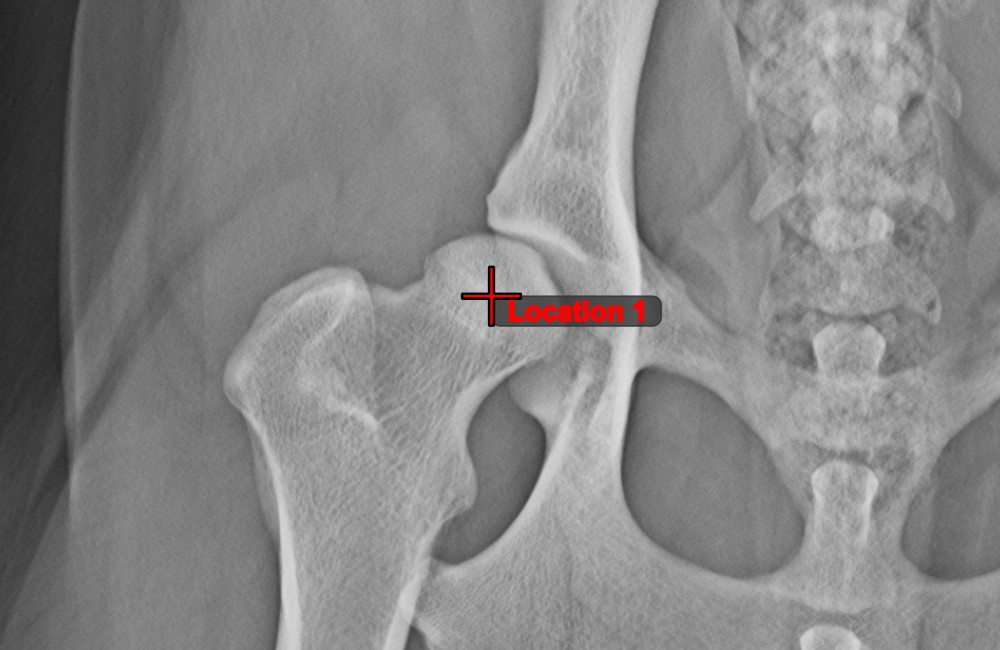

Center Point of Line¶

Identify and mark the center point of a new or existing line measurement on the scene by using the Center Point of Line

tool.

Select the tool from the left toolbar and assign it to one of the available mouse buttons. Place the start and end points on the scene, select them from already existing points on the image, or select an already drawn line from the scene. The center point of the line will be automatically calculated and placed on the scene. The center point of each line will always be marked with the letter C.